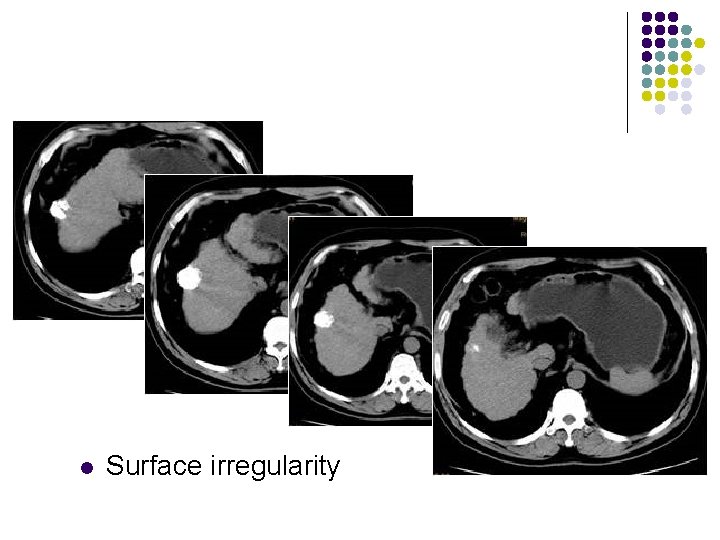

Hepatic Cirrhosis l l Surface irregularity Increased echogenicity Heterogeneous coarse echotexture Ascites

l Surface irregularity